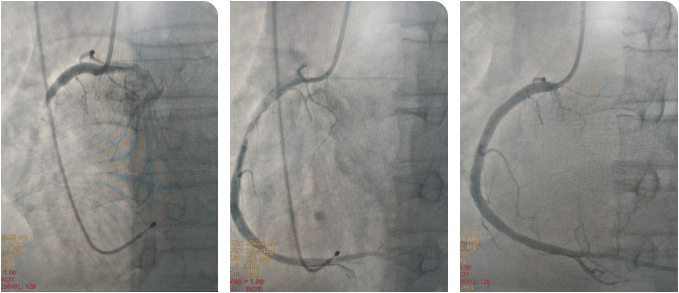

时间就是生命!心内科介入团队与死神展开较量,大家轮流为患者进行心肺复苏,并以最快的速度完成消毒、铺巾。患者大动脉搏动消失,李新国主任、吴利杰主任凭借扎实的基本功,盲穿腋静脉及右侧股动脉,植入临时起搏器。根据心电图判断罪犯血管为右冠状动脉,李新国主任果断直接选择右冠指引导管造影,造影证实判断,右冠状动脉粗大,自近段完全闭塞。12:36介入团队将导丝送到了患者闭塞血管的远端,并用球囊对闭塞血管扩张后顺利恢复前向血流。奇迹出现了,患者微弱的心跳逐渐有力,血压、心律也逐渐好转。此时的患者仍处于昏迷状态,携带呼吸机及临时起搏器转入CCU病房继续治疗。

术后,在李新国主任、沈靖超主治医师及段秋燕护士长带领的护理团队精心施治、细心护理下,患者于当日意识转清醒,拔除气管插管,生命体征稳定,之后也顺利渡过心梗后心力衰竭、消化道应激性溃疡、肺部感染等并发症,3天后拔除临时起搏器,1周后于右冠状动脉动脉植入2枚支架,之后转入普通病区继续巩固治疗,并于近期顺利出院。